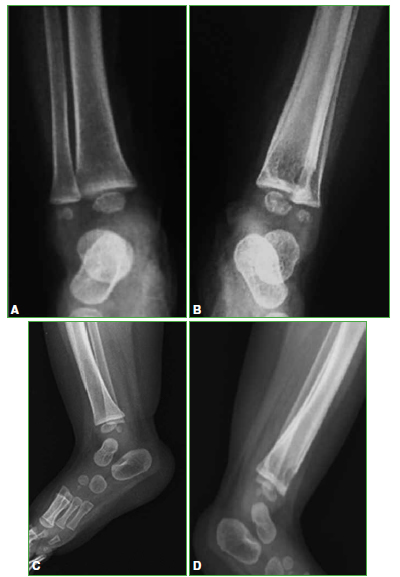

La evolución de la paciente fue muy favorable, sin dolor, ni secuelas motoras, ni daño esquelético residual, sin compromiso de la fisis, ni del crecimiento del miembro. Se puede observar la evolución de la lesión ósea en los controles radiográficos posoperatorios (Figuras 3-5).

Figura 5.

Radiografías de frente y de perfil, de ambos tobillos, a los 2 años y 6 meses de la intervención.